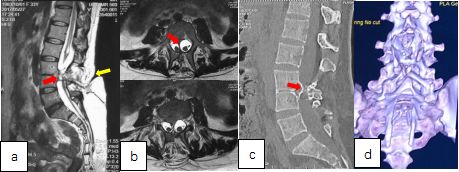

患者术前影像学检查。

MRI检查矢状位(图a)可见椎腰3、4水平椎管内横行骨棘(红色箭头处),脊髓内局部异常信号,横断位(图b)可见脊髓分为左右两支,脊髓位于左右两支脊髓之间。另可见患者背部皮毛窦、终丝增粗、双棘突畸形。CT(图c)可见腰3、4椎体分节不全,部分融合,骨棘为高密度,考虑为骨性。棘突形态欠规则。CT三维重建(图d)可更直观反映双棘突及骶椎裂的情况。

该患者术前几乎涵盖了脊髓纵裂畸形的所有临床表现,包括皮肤表现、二便症状、下肢力量等。患者症状由“腰麻”后突然加重,考虑可能由腰椎穿刺脊髓损伤导致,因此此类患者脊髓圆锥低位、张力高,硬膜下麻醉应非常谨慎,临床上如遇腰骶部毛发、皮毛窦等异常表现的,应高度怀疑脊髓纵裂或脊髓拴系,需行相关检查确认。